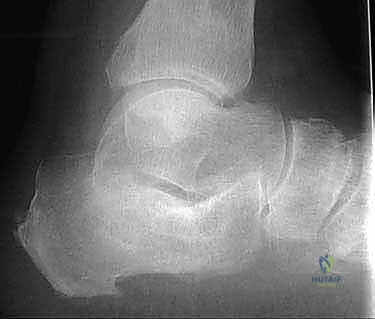

- الأشعة السينية (X-rays) متعددة الزوايا: لتقييم الانهيار العظمي وزوايا الكعب (مثل زاوية بوهلر وزاوية جيسان).

- الأشعة المقطعية ثلاثية الأبعاد (3D CT Scan): وهي الخطوة الذهبية والأهم في عيادة الدكتور هطيف. تتيح هذه الأشعة بناء نموذج ثلاثي الأبعاد دقيق للكعب المشوه، مما يسمح بتحديد أماكن الانحشار العظمي بدقة المليمتر، ومعرفة مدى تلف الأسطح المفصلية. بناءً على هذه الصور، يتم وضع خطة "القطع العظمي التصحيحي" قبل دخول غرفة العمليات.